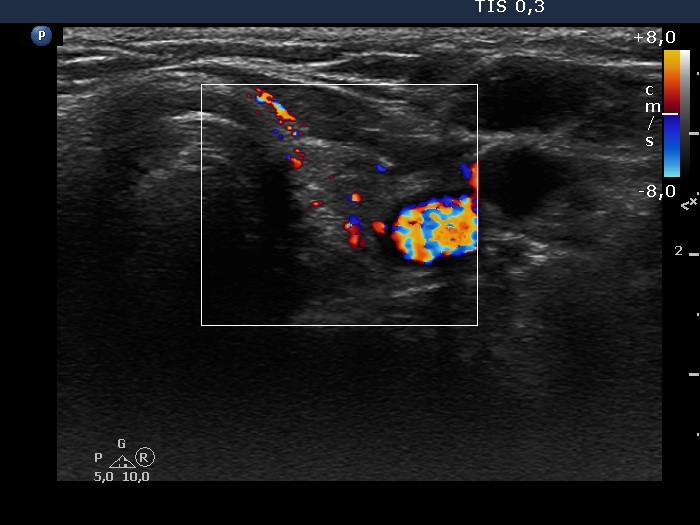

Left lobe, transverse view, color Doppler mode. The vascularization is average.